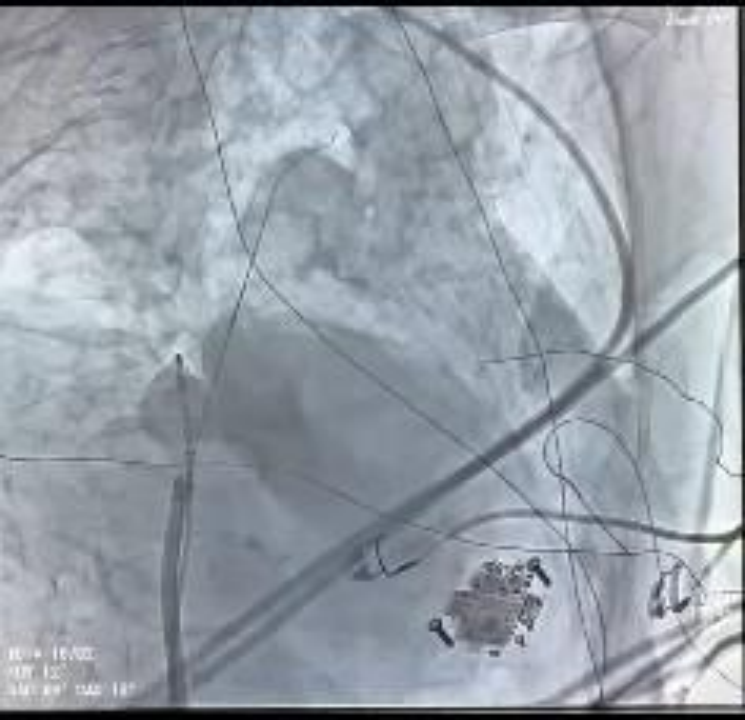

术中造影显示患者下腔静脉极度迂曲,无法经常规途径送入导管。团队及时调整手术路径,改为左腋静脉入路,采用 AccuSafe 穿刺导丝联合 Navigo 8.5Fr 可调弯鞘完成房间隔穿刺,并运用医院首创 Y 阀造影剂显影方法确认进入左房。术中依托可调弯鞘与导丝双重安全保护机制,避免误穿与组织损伤,精准完成穿间隔操作。随后送入 Farapulse PFA 导管,完成双侧肺静脉及上腔静脉消融隔离,累计放电 37 次,电位完全阻断,手术顺利成功。

术中下腔静脉影像

电生理团队实施经左腋静脉入路 PFA 手术